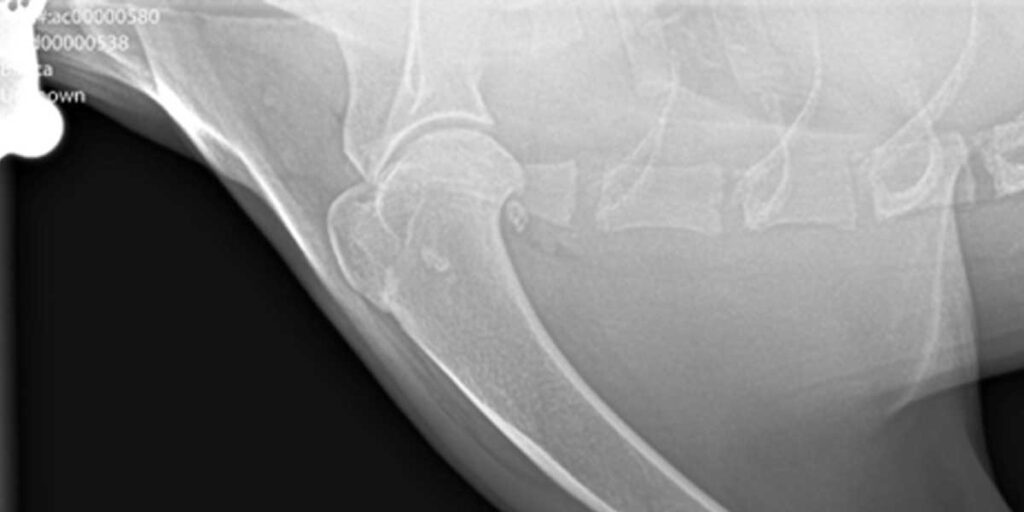

Sindrom objedinjuje skup anatomskih promjena: suženje nosnica i nosnih prohoda, zadebljanje i otečenje sluznice dišnih prohoda, preveliki jezik za njihovu kratku lubanju, produljenje i zadebljanje mekog nepca koje zatvara ulaz u dušnik, kolabiranje grkljana i dušnika koje smanjuje njihov promjer. To dovodi do niza sekundarnih patologija koje nastaju zbog kronične upale i smanjenog dotoka kisika u stanice. Uz poteškoće s disanjem mogu se javiti i gastrointestinalni problemi poput hijatalne hernije (prolazak organa trbušne šupljine kroz ošit), stenoze pilorusa i gastro – ezofagealnog refluksa. Sindrom se često poistovjećuje s opstruktivnom apnejom tijekom spavanja u ljudi.